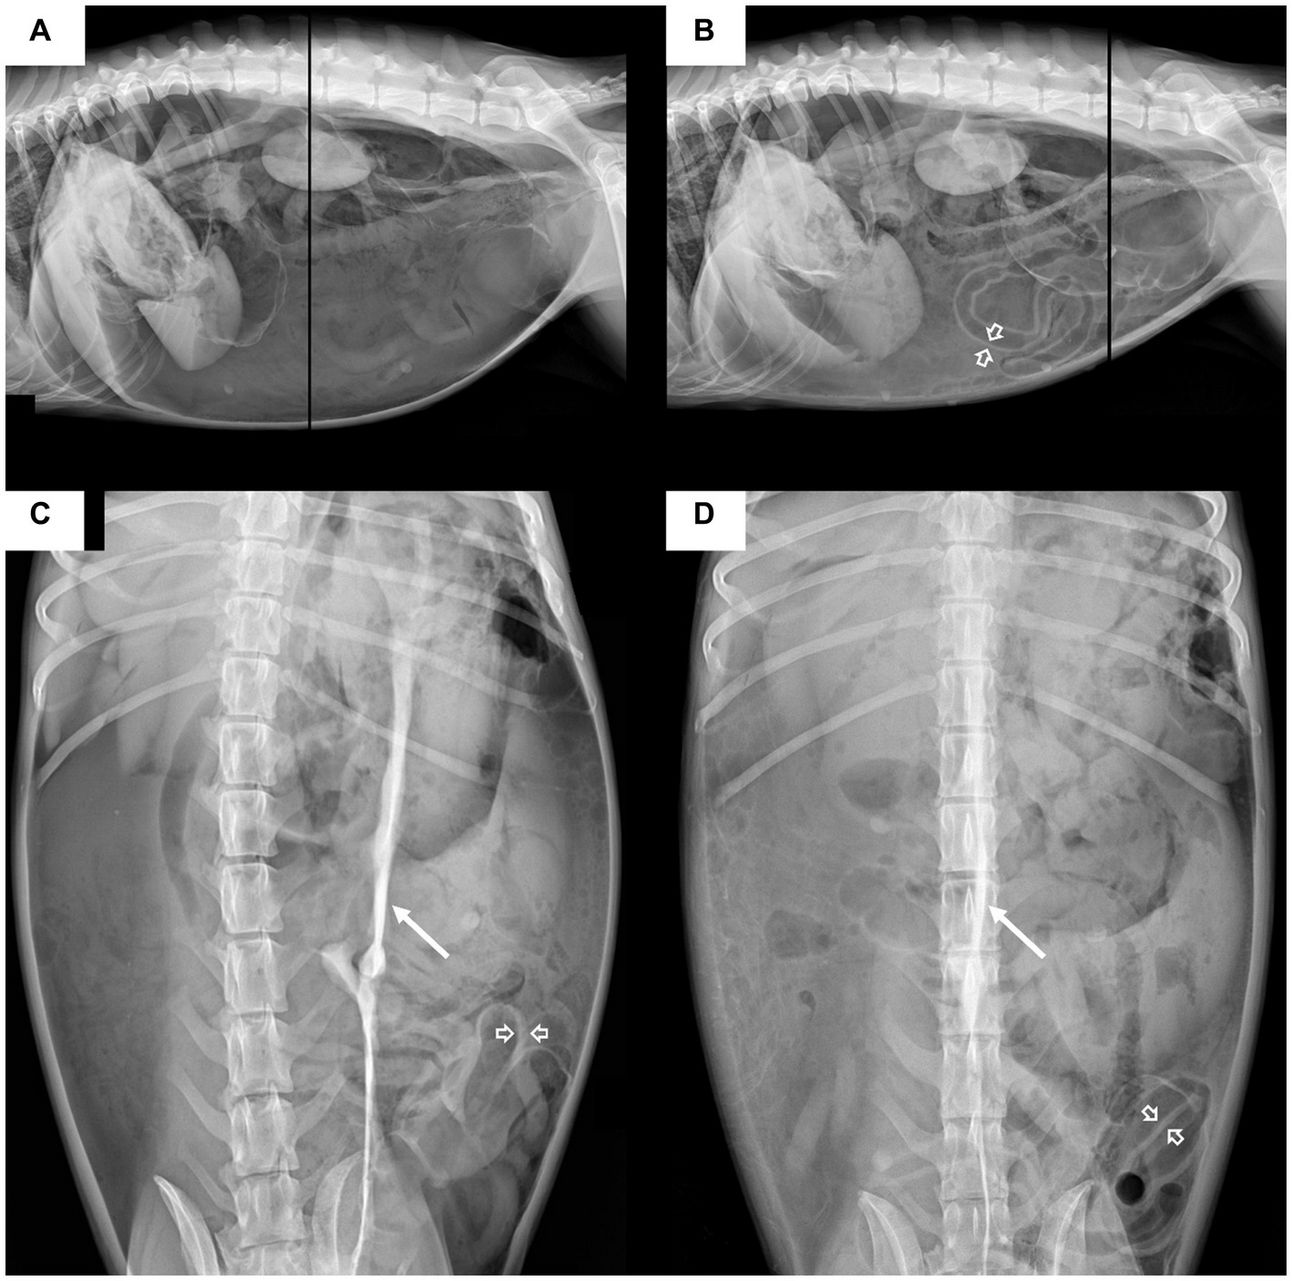

Lateral (A,B) and ventrodorsal (C,D) abdominal radiographic projections of the dog. The images on the left (A,C) were obtained before decompression, and those on the right (B,D) were obtained immediately after decompression. Before decompression, massive pneumoperitoneum is characterized by the outlining of the peritoneal cavity with massive amount of gas and outlining of both sides of the small bowel wall with peritoneal gas (open arrow); a decreased overall abdominal serosal detail is also noted. On the ventrodorsal (C) radiograph, a radiopaque stripe (arrow) is identified in the mid-abdomen, which is considered a peritoneal ligament. After decompression, the abdominal distension decreased, but a large amount of free gas is still present. Cranial displacement of the diaphragm indicates increased intraperitoneal pressure.